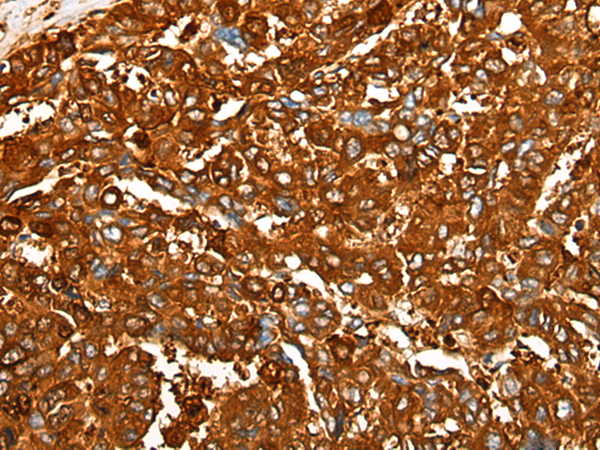

分类: 科研抗体货号: P12873别名: C35; ORB3; XTP4; RDX12; C17orf37应用: IHC反应种属: Human, Mouse